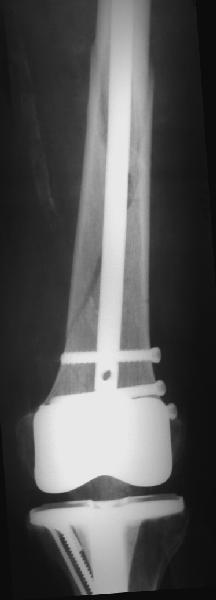

В приложении - недавний перипротезный перелом.

Вложение не в текстовом формате было извлечено&hellip;

Имя     : 2get_image.jpg

Тип     : image/jpeg

Размер  : 7863 байтов

Описание: отсутствует

Url     : http://weborto.net:8080/pipermail/ortho/attachments/20110903/40f50831/attachment-0007.jpg